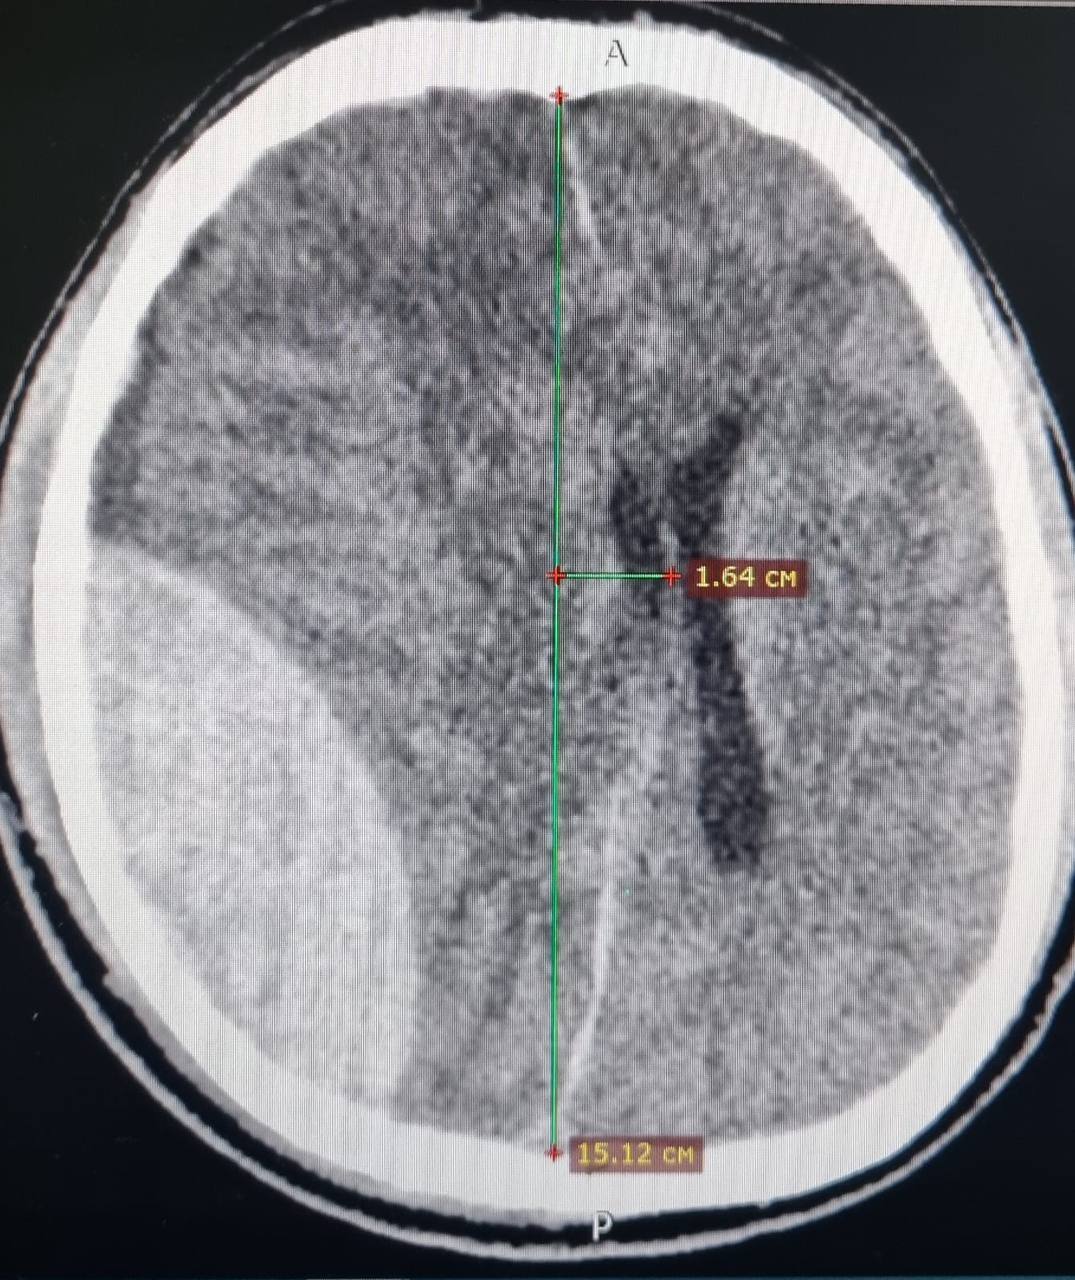

На серии КТ-снимков врачи выявили перелом черепа с эпидуральной гематомой, вызвавшей отёк мозга и смещение его срединных структур. Это скопление крови между костями черепа и мозгом — крайне опасное и редкое, на его долю приходится меньше 2% всех случаев.